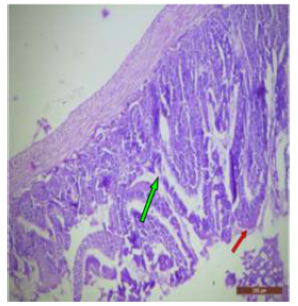

In fluoridated rats damaged and broken villi, focal intervillous haemorrhages and ulceration was present (Figure 12). There was shortening and flattening of some of the villi (Figure 13), distorted crypts, large swollen goblet cells lined by columnar epithelium with wide spaces were present (Figure 14). Distortion of different layers of mucosa with the loss of villous architecture and shedding of surface epithelium was seen in the jejunum of fluoridated rats (Figure 15). The villus architecture was notably disturbed, with a marked loss of crypts. Furthermore, there was a noticeable decrease in the number of goblet cells (Figure 16). The villi appeared scattered and fragmented, indicating a disruption in their typical architecture. Reduction in size of intestinal glands highlighted the detrimental impact of fluoride exposure on the intestinal morphology of rats (Figure 17).

Figure 12: T.S. of jejunum of rat treated with 600 mg NaF/kg b.w./day for 40 days showing ulceration, focal intravillous hemorrhages and broken villi (↑). H&E × 100.

The ileal mucosa of control rat was built up of numerous folds forming the villi, through which connective tissue of the lamina propria containing tubular glands i.e., crypts of Leiberkühn were present (Figure 18). The epithelial lining of the villi was composed of Paneth cells and intestinal glands (Figure 19). In fluorotic rats, there were abnormal shaped, damaged and broken villi with bulbous tips. Lymphatic dilation and haemorrhaged in lamina propria were also seen (Figure 20). In the ileal mucosa, prominent inflammation, distortion of crypts with shredded cells inside the crypts were visible (Figure 21). Swollen and necrotic crypts were present (Figure 22). The ileal tissue showed disruptions in the normal mucosal architecture with signs of villous atrophy and cell infiltration (Figure 23). Lymphatic infiltration was prominent and numerous enlarged lymph nodules appeared in lamina propria of villi. There were ill-defined cell boundaries, vacuolated cytoplasm and pyknotic nuclei (Figure 24).

Figure 13: T.S. of jejunum of rat treated with 600 mg NaF/kg b.w./day for 40 days showing distortion, shortening and flattening of villi (↑). H&E × 100.

Figure 15: T.S. of jejunum of rat treated with 600 mg NaF/ kg b.w./day for 40 days showing atrophy of villi and distortion of different layers and destruction of surface epithelium (↑). H&E × 100.

Figure 16: T.S. of jejunum of rat treated with 600 mg NaF/ kg b.w./day for 40 days showing disruption of villi (↑), reduction in number of goblet cells (↑) and crypt loss (↑). H&E × 100.

Figure 17: T.S. of ileum of control rat showing scattered and broken villi (↑) and decrease in size of intestinal glands (↑). H&E × 100.

Fluoride is a widely recognized environmental pollutant with potential adverse effects on various biological systems. The small intestine, being a critical component of the digestive system, is particularly susceptible to fluoride toxicity. One of the most significant structural alterations observed in the small intestine due to sodium fluoride exposure is villus atrophy. The villi, which are finger-like projections lining the intestinal wall, play a crucial role in nutrient absorption by increasing the surface area. Studies have shown that fluoride exposure leads to a marked shortening and thinning of these villi, significantly reducing their surface area [12]. Histopathological examination revealed that the villi in fluoride-exposed rats were not only shortened but also exhibited a disorganized and fragmented appearance. The villus tips often showed signs of blunting and fusion, further contributing to the reduction in effective absorptive surface area. This morphological change was accompanied by decrease in the number of microvilli on the epithelial cells, exacerbating the absorption issues [13]. Sodium fluoride exposure induces significant degeneration of the intestinal mucosa. This degeneration includes various pathological changes such as epithelial cell shedding, vacuolation, and necrosis [14]. Goblet cells, which secrete mucus, play a vital role in protecting the intestinal epithelium by forming a protective mucus layer. Sodium fluoride exposure leads to a significant reduction in the number of goblet cells, resulting in decreased mucus secretion. The structural alterations, particularly villus atrophy and mucosal degeneration, lead to a significant reduction in the absorptive surface area of the small intestine [15].

The loss of goblet cells and the associated decrease in mucus production compromise the intestinal barrier function [16]. This barrier dysfunction makes the intestine more permeable to pathogens, toxins, and antigens. Sodium fluoride induces an inflammatory response into the mucosa and submucosa. This chronic inflammation can further exacerbate tissue damage and impair intestinal function [17]. The histopathological changes observed in this study are consistent with those reported in other studies. It has been previously shown that fluoride exposure leads to villous atrophy and mucosal inflammation [18]. The use of scanning electron microscopy provides detailed insights into the surface changes occurring at the cellular and subcellular levels in response to NaF exposure. Studies have demonstrated that sodium fluoride induces significant alterations in the structural integrity of the small intestine in rats. These changes can be observed through SEM, highlighting the extent of damage and providing a better understanding of the underlying mechanisms.